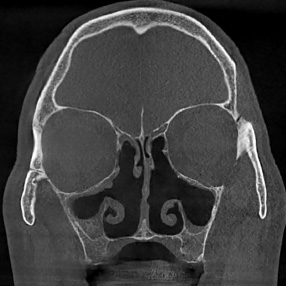

※ 축농증 수술 후 생길 수 있는 부작용으로는 출혈, 감염, 염증이 있을 수 있습니다.

본 사진은 의료기관에서 진료를 본 환자이고, 전후 사진 인물이 동일인이며,동일조건에서 촬영이 되었습니다.